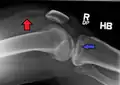

![]() | |

| A severe tibial plateau fracture with an associated fibular head fracture | |

Lipohemarthrosis (presence of fat and blood from bone marrow in the joint space after an intraarticular fracture) seen on X-ray in a person with a subtle tibial plateau fracture

Lipohemarthrosis due to a tibial plateau fracture